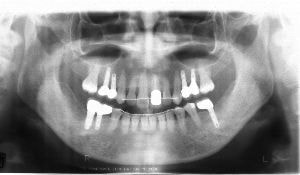

治療例1 (インプラント補綴+矯正)